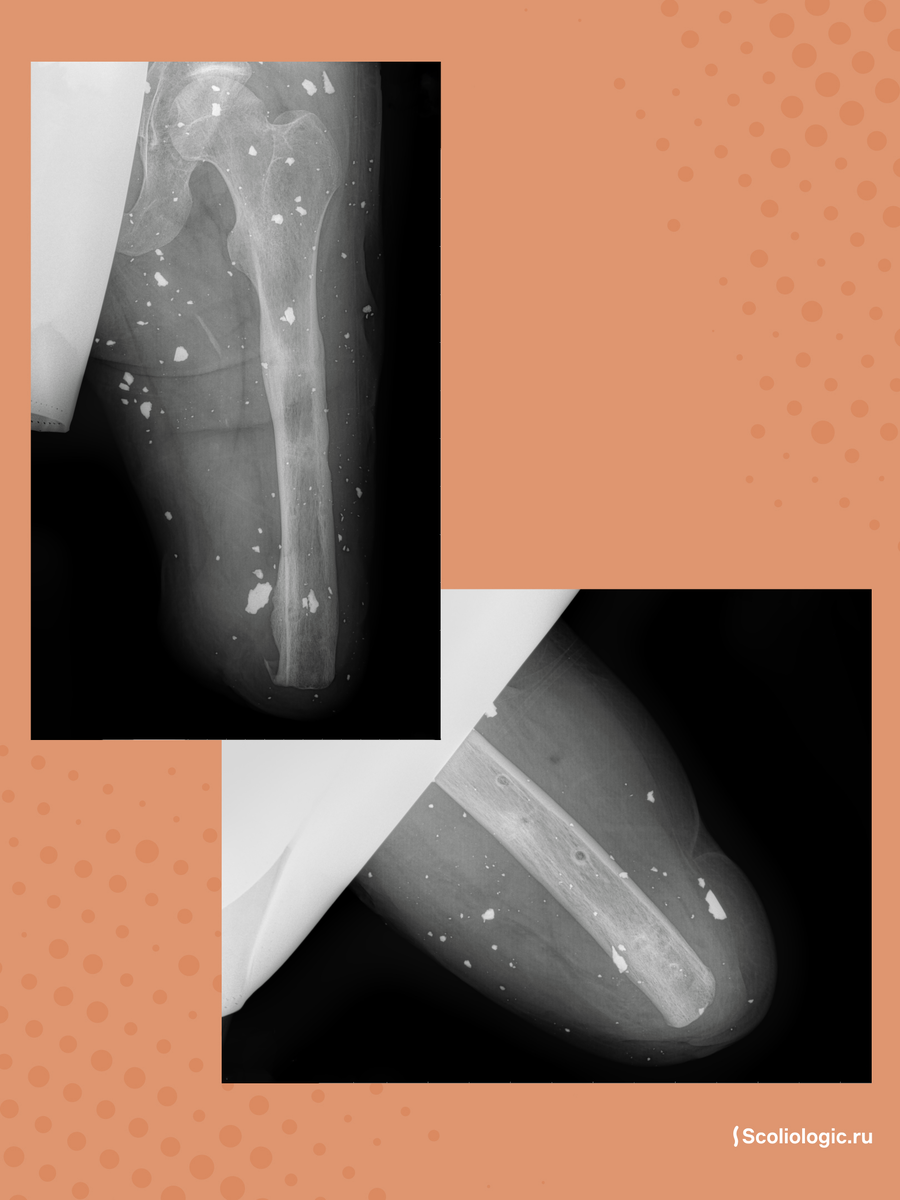

В «Сколиолоджик» обратился военнослужащий с непростой ситуацией: после серьезной травмы ему ампутировали левую ногу на уровне голени, а правая нога получила множественные оскольчатые переломы всех костей. Около года пациент провел в аппарате Илизарова без нагрузки на конечность, часть переломов успешно срослась.